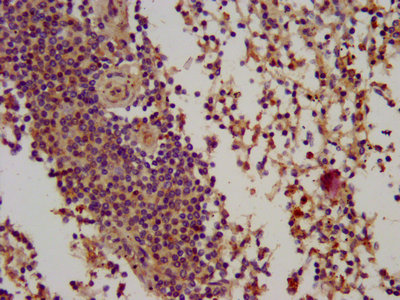

IHC image of CSB-PA002701LA01HU diluted at 1:100 and staining in paraffin-embedded human lymph node tissue performed on a Leica BondTM system. After dewaxing and hydration, antigen retrieval was mediated by high pressure in a citrate buffer (pH 6.0). Section was blocked with 10% normal goat serum 30min at RT. Then primary antibody (1% BSA) was incubated at 4°C overnight. The primary is detected by a biotinylated secondary antibody and visualized using an HRP conjugated SP system.

IHC image of CSB-PA002701LA01HU diluted at 1:100 and staining in paraffin-embedded human spleen tissue performed on a Leica BondTM system. After dewaxing and hydration, antigen retrieval was mediated by high pressure in a citrate buffer (pH 6.0). Section was blocked with 10% normal goat serum 30min at RT. Then primary antibody (1% BSA) was incubated at 4°C overnight. The primary is detected by a biotinylated secondary antibody and visualized using an HRP conjugated SP system.